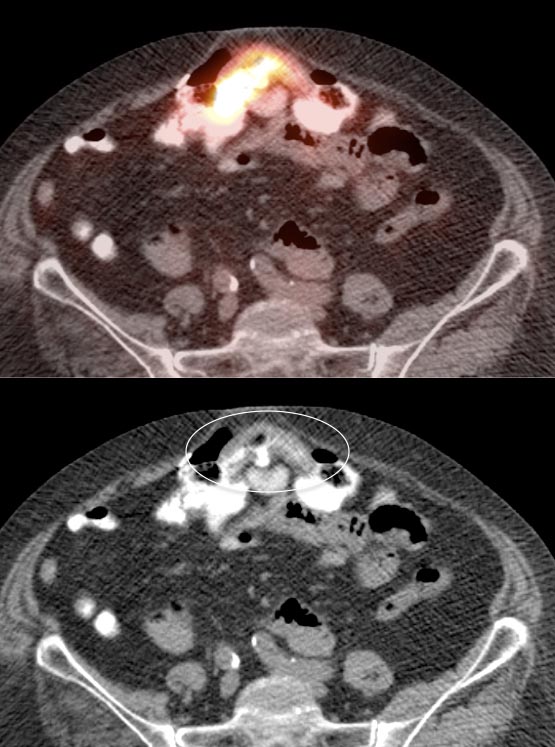

After the stomach, normal intense colon uptake is the most over-called “abnormality” by the inexperienced PET/CT radiologist.

The colon — focally or diffusely — often demonstrates intensely uptake of FDG.

Proposed mechanisms for colonic uptake of FDG include muscle contractions, the presence of lymphoid tissue and intraluminal contents.

The most common sites of normal physiologic intense colon uptake are the cecum and the distal rectum.

Generally, colonic uptake should be considered normal unless:

• There is an accompanying CT abnormality (e.g. focal bowel wall thickening or focal mass); or

• A solitary focus of intense uptake presents in an otherwise non-avid (or minimally avid) colon.  Although this focal uptake may still represent normal physiologic uptake, it is reasonable to raise the possibility of a small polyp and recommend colonoscopy (polyps are rarely visible on the CT images).

We generally report, “As an adenomatous polyp or other pathology cannot be excluded, further evaluation with colonoscopy may be warranted, if not recently performed.”